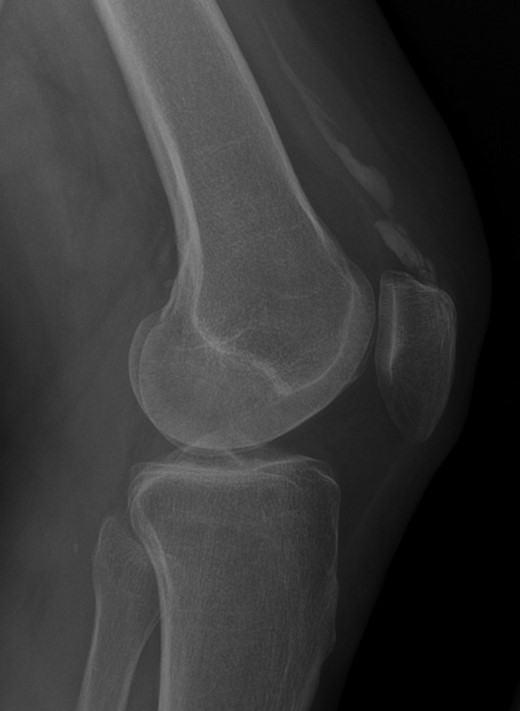

Plain radiographs and an MRI scan of the left knee were undertaken.

Radiographic appearance and MRI signal change confirmed calcification rather than ossification or enthesopathy. An unusual diagnosis of dystrophic calcification of the left quadriceps tendon was made (Figs 1–4).

Weight-bearing lateral radiograph of the patient’s knee shows extensive mineralization of the quadriceps tendon.